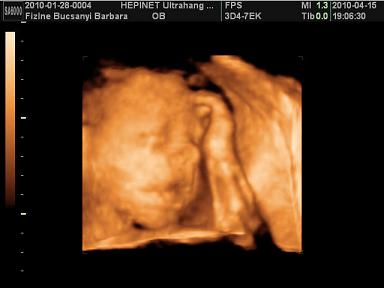

Edi, Bibar: gratu a jó UH-os hírekhez, Kamilláról várjuk ám a képeket, Boti pedig édes kis ManóPofi!